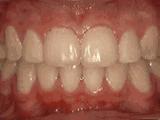

4、牙列拥挤,前牙没有咬合,上下牙齿中线不对称,牙弓狭窄,上颌“*牙虎**”异位生长,经专业评估没有拔牙,经过矫正后的牙齿是这样的~